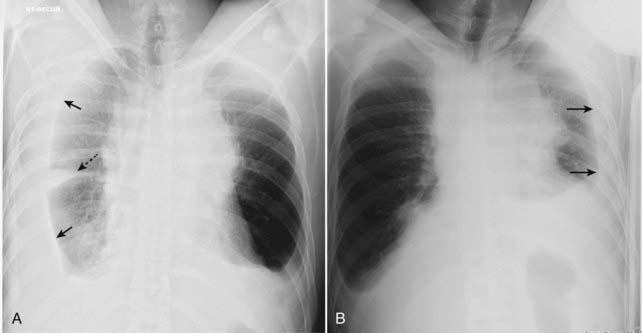

Figure 6-9 Decubitus views of the chest.

A, A right lateral decubitus view of the chest. The film is exposed with the patient lying on the right side on the examining table while a horizontal x-ray beam is directed posteroanteriorly (PA). Because the patient’s right side is dependent, any free-flowing pleural fluid will layer along the right side (solid black arrows), forming a bandlike density. Notice how the fluid flows into the minor fissure (dotted black arrow). B, A left lateral decubitus view of the chest. When the same patient lies on the table with the left side down, free fluid on the left side layers along the left lateral chest wall (solid black arrows). This patient has pleural effusions from lymphoma.